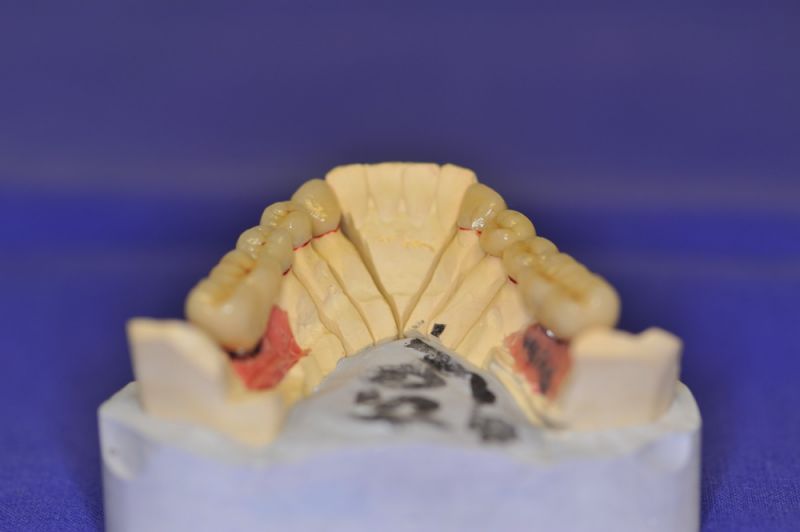

Mit dem heutigen Tag geht eine der technisch schwierigsten und anspruchsvollsten Arbeiten zu Ende, die im CMD-CENTRUM-KIEL jemals erstellt worden ist. Dabei sind es nur 10 Kronen, die benötigt werden, um die starken Kopf- und Gesichtsschmerzen der Patienten zu beseitigen.

4. Notwendigkeit die Mundhygienefähigkeit der Arbeit auch unter sehr beengten Verhältnissen zu schaffen, um der Arbeit eine günstige Prognose mitzugeben.